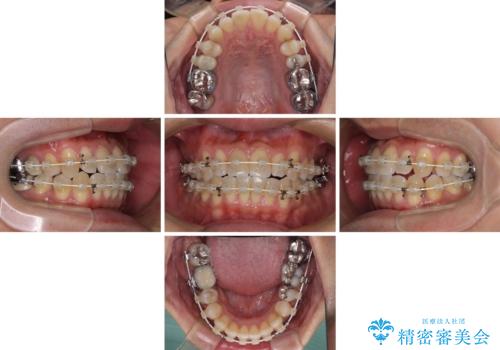

- 審美装置

ワイヤー矯正でもマウスピース矯正でも対応可能とお伝えし、非常に悩まれていましたが、2年後に転勤の可能性が高いとのことで、治療終了までの期間を想定しやすいワイヤー矯正にて治療を行うこととしました。

前歯のクロスバイトは、改善の途中で歯髄壊死を起こすリスクが高くなるため、マウスピース矯正よりもワイヤー矯正をお勧めしております。

この患者様もクロスバイトはあっという間に改善され、1年強で速やかに治療を終えることができました。